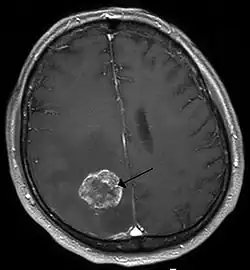

Brain metastasis in the right cerebral hemisphere from lung cancer, shown on magnetic resonance imaging

SpecialtyNeurosurgery, neuro-oncology